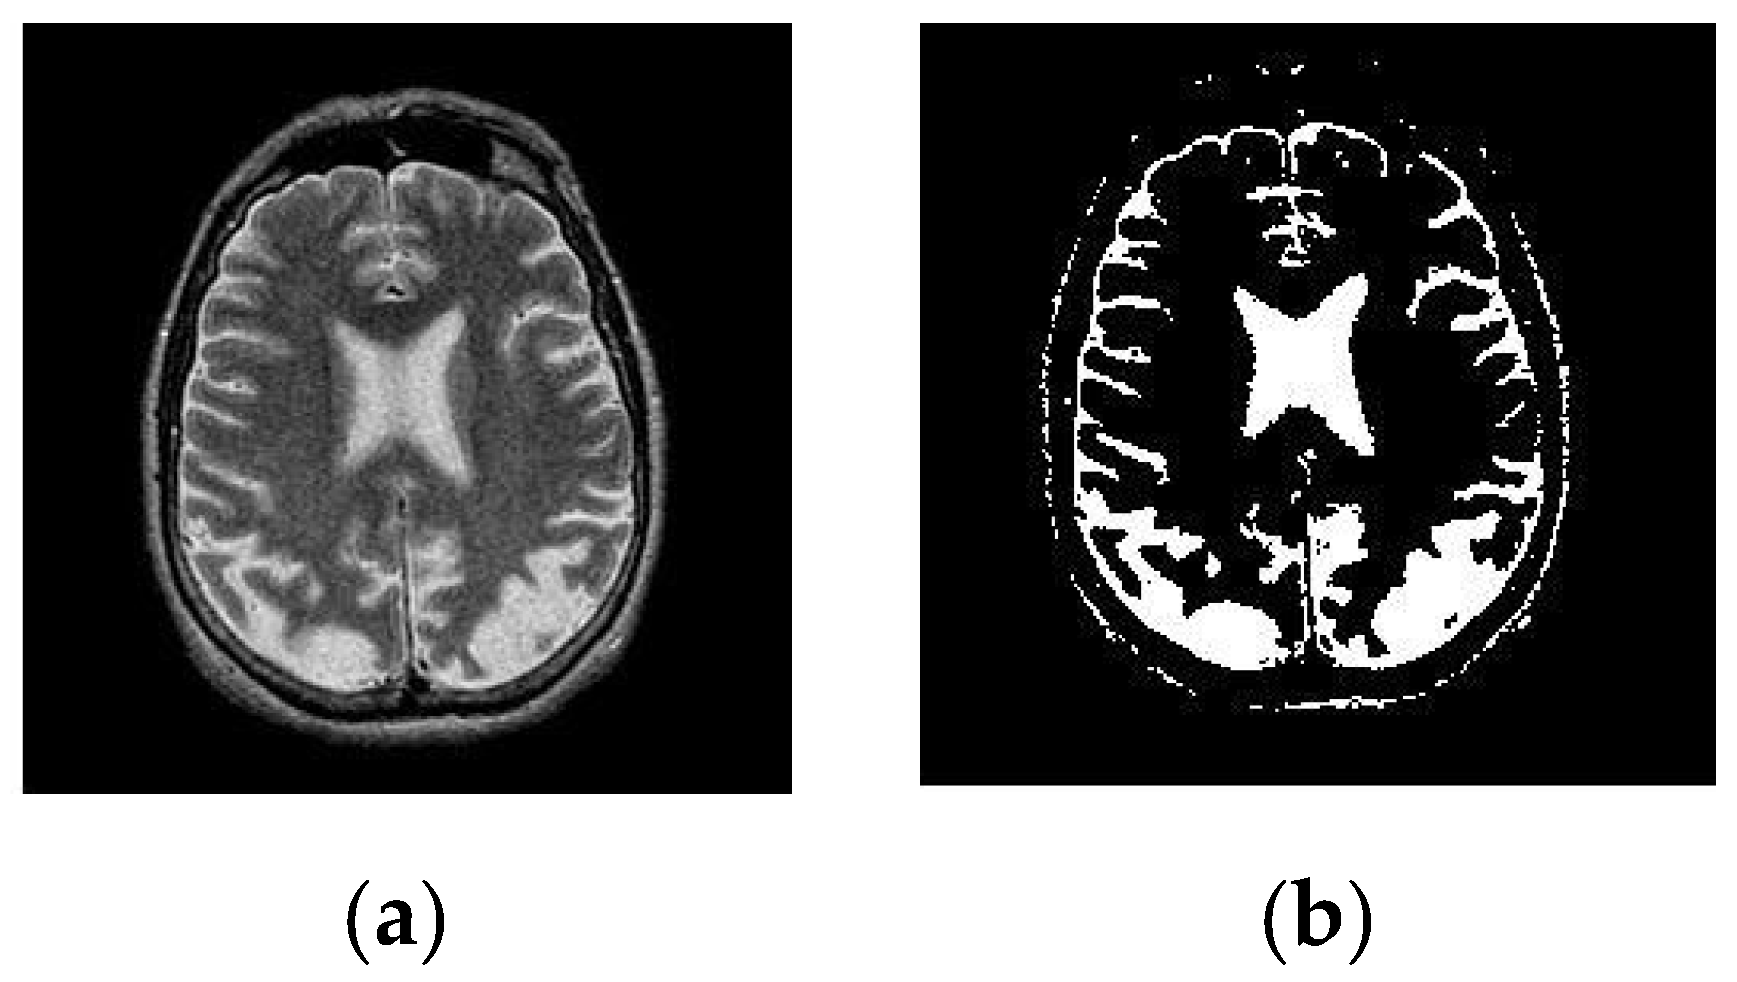

3.2. Segmentation

5.2. Result 2: Experiment with T-1 Weighted MRI Image Dataset

- (a)

- Abnormality Classification for T-1 Weighted Images

- (b)

- T-1 Weighted Image Tumor Classification